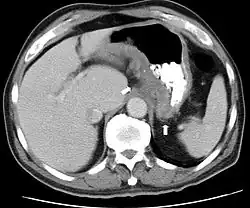

CT and MRI scans are useful for evaluating the small bowel with enteroclysis protocols.[168] They are also useful for looking for intra-abdominal complications of Crohn's disease, such as abscesses, small bowel obstructions, or fistulae.[169] Magnetic resonance imaging (MRI) is another option for imaging the small bowel as well as looking for complications, though it is more expensive and less readily available.[170] MRI techniques such as diffusion-weighted imaging and high-resolution imaging are more sensitive in detecting ulceration and inflammation compared to CT.[171][172]